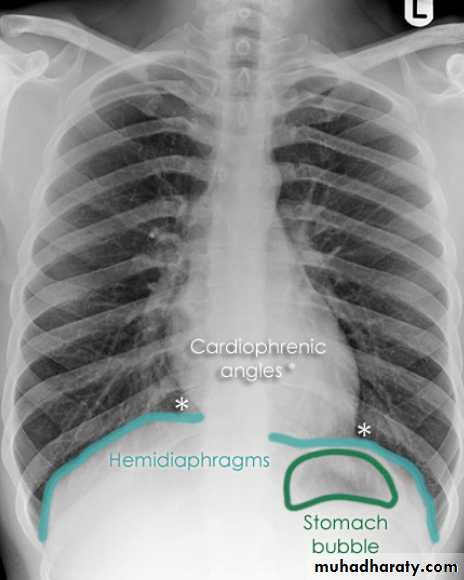

Look carefully on both diaphragmatic cruse costo & cardio phrenic angles

Pleural effusion

50.pleural effusion

51.pleural effusion .